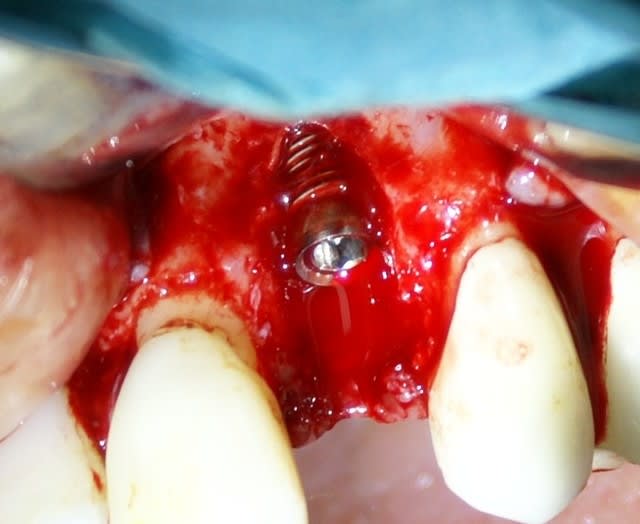

Tout à fait d'accord growler et c'est d'ailleurs ce que l'on peut voir sur le cas suivant. Fracture radiculaire, aucune infection periradicualire. Extraction et implantation immediate. Espace existant entre l'implant et l'alvéole est comblé par du BioOss. Un logement sous gingival est formé en vestibulaire et palatin de facon à pouvoir recouvrir le tout par BioGide et un conjonctif enfoui.

L'implant est de 15mm mais l'alvéole était large et 50% environ de la surface implantaire n'était en contact qu'avec du BioOss. J'ai pour cela préféré enfouir.